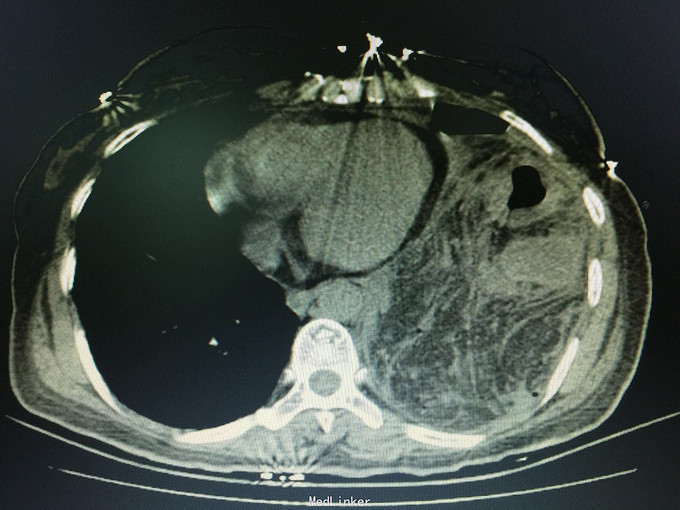

女,41岁, 主诉:腹部胀痛伴不排便、不排气1周, 现病史:一周前无诱因开始腹部胀痛,逐渐加重,以左上腹明显,不排便,不排气,恶心,呕吐数次胃内容物,在当地医院抗炎治疗不见好转,今排腹部平片诊断为“肠梗阻”,来诊。

一般状态可,腹部平坦,未见肠型及蠕动波,脐周压痛,左上腹明显,无腹肌紧张,未及包块,移动性浊音阳性,肠音2次/分。 辅助检查:全腹CT:腹部肠管明显扩张,积液,左侧膈肌局部缺损,腹腔内肠管及系膜组织疝入胸腔。

诊断:膈肌疝,疝内容嵌顿,肠梗阻 处理:手术治疗。